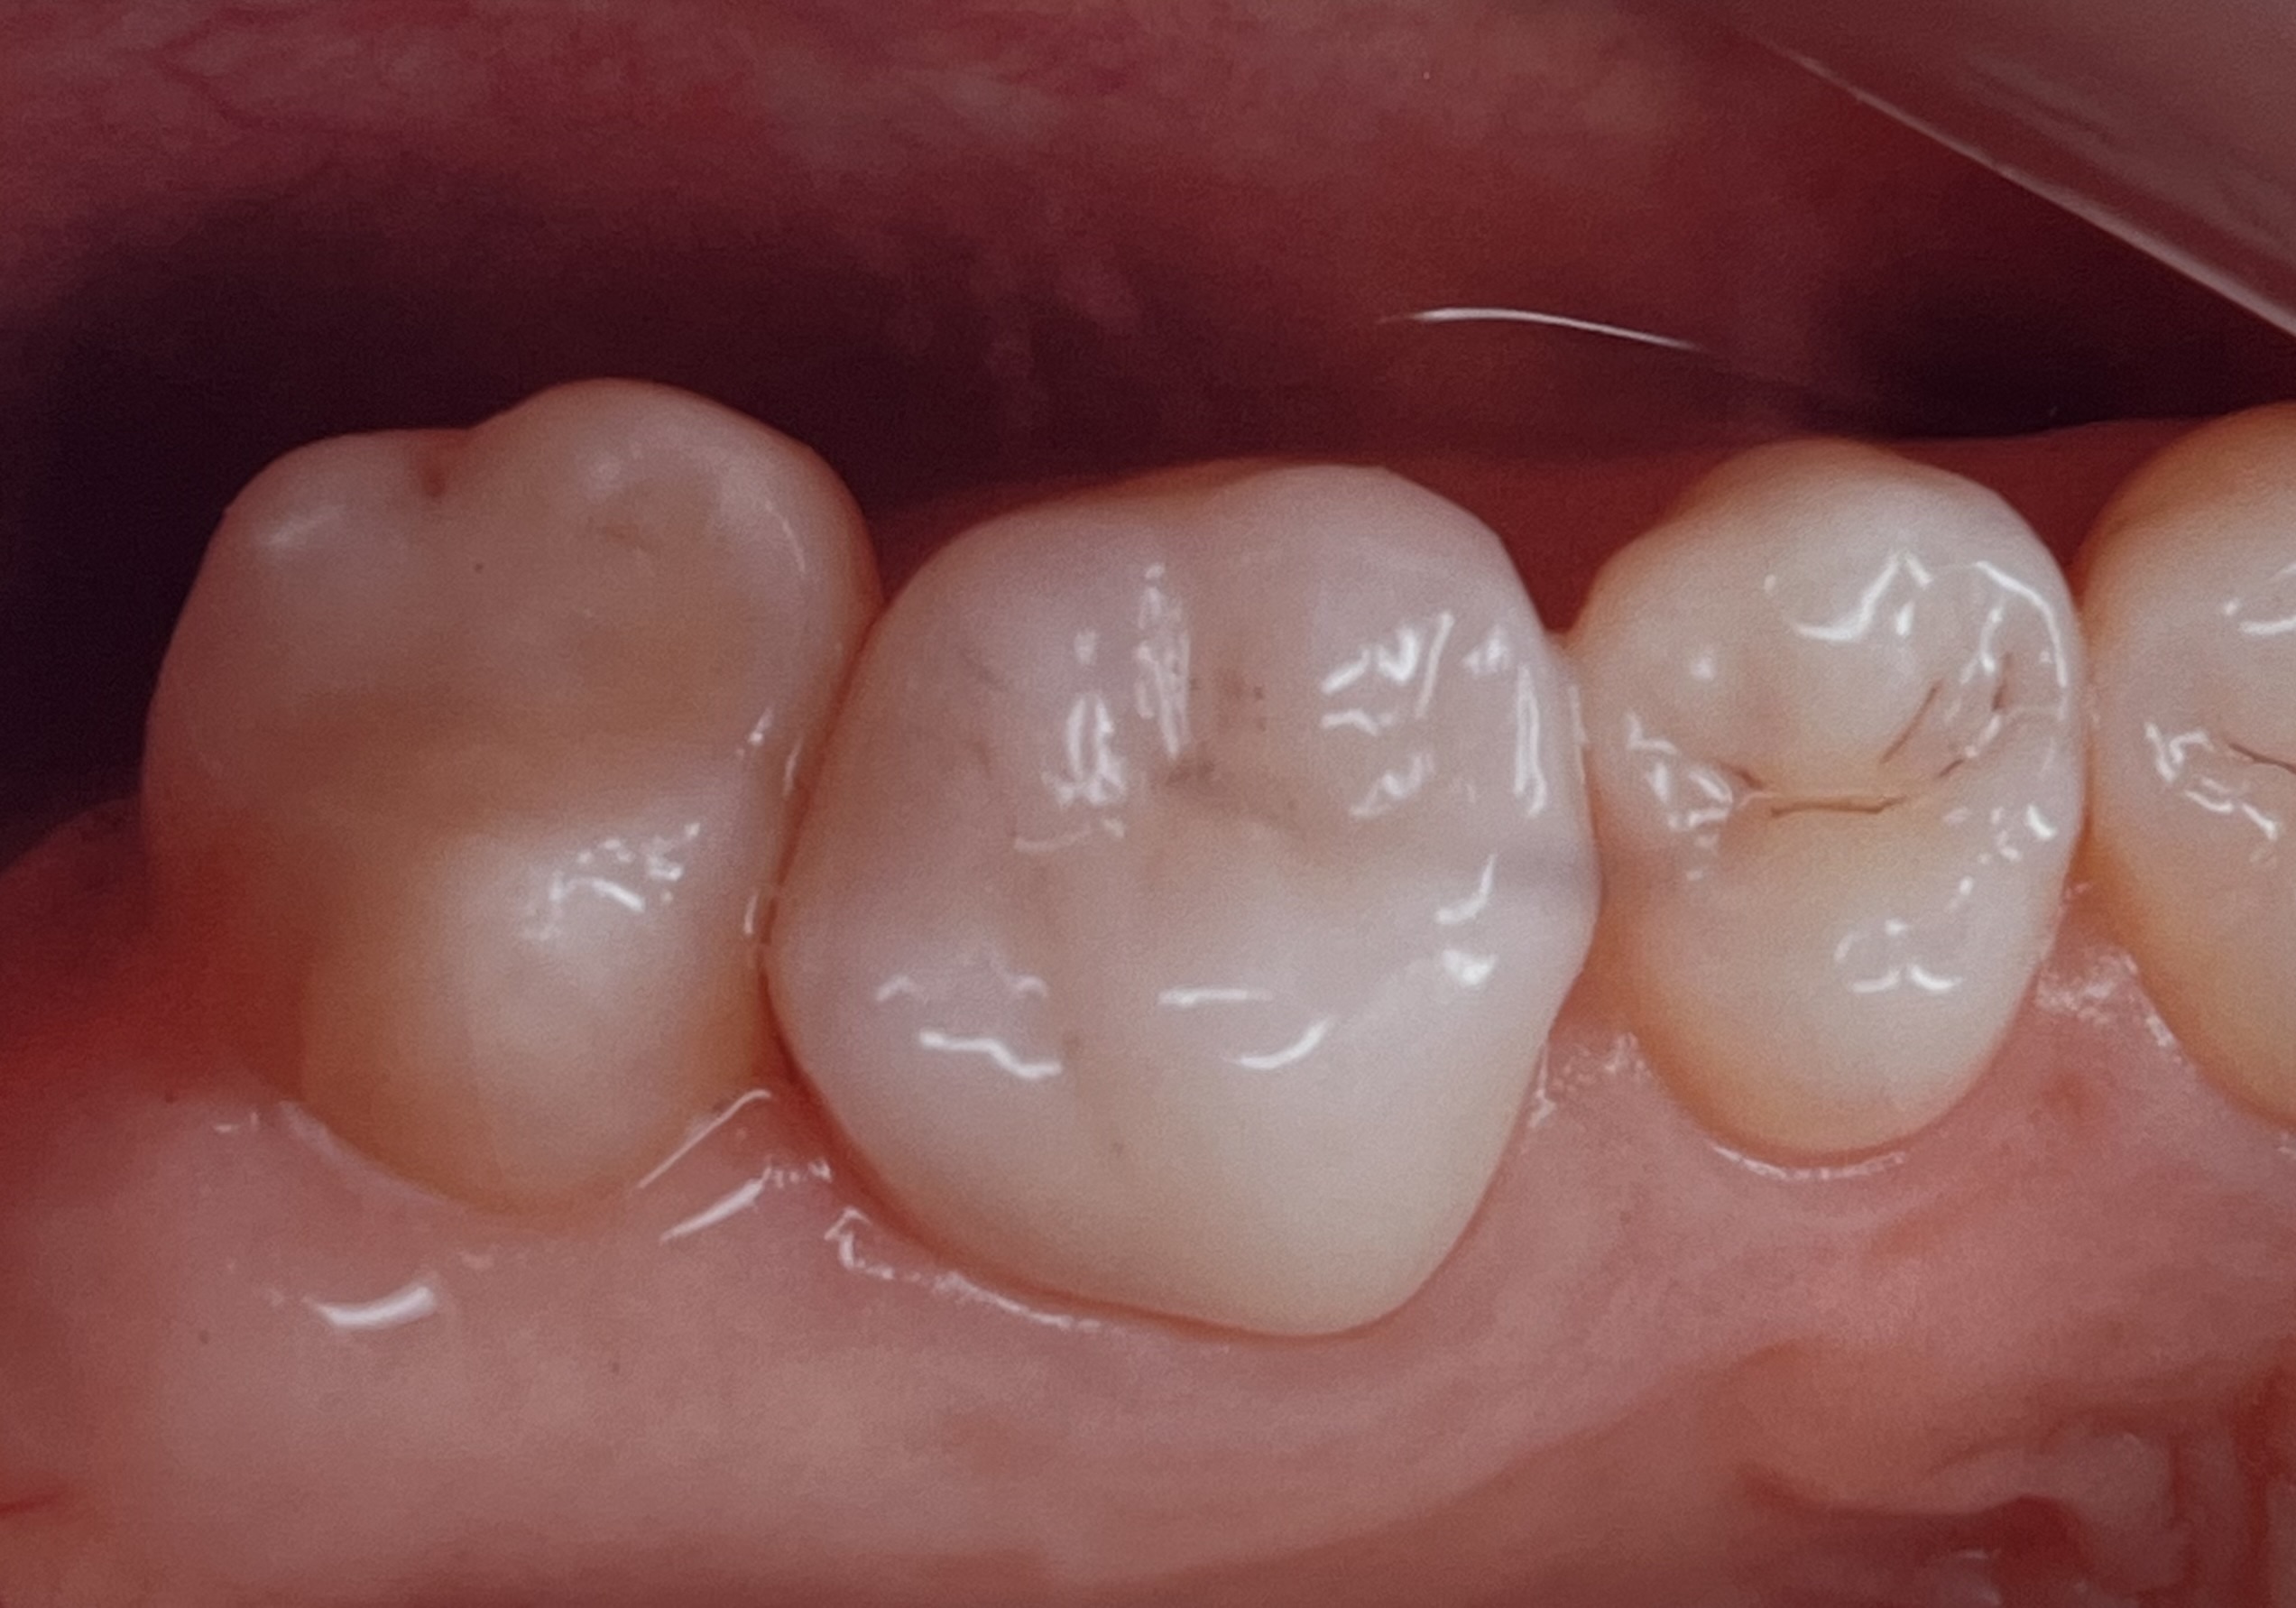

今回の治療例は、ジルコニアセラミッククラウンとエナミックセラミックインレーです。

1番左の歯が、エナミックセラミックインレーです。

左から2番目の白い歯は、ジルコニアセラミッククラウンです。セラミックなのでエナミックと特徴は似ていますが、ジルコニアは強度がさらに強く奥歯に特に向いています。